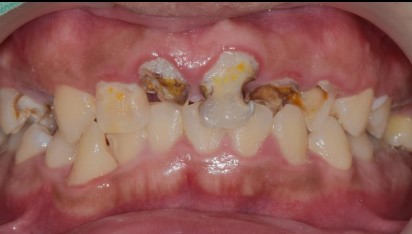

任何治療都必須做審慎評估,表面看見的問題不代表全部。 例如這位陳先生主訴是想門牙做假牙+恢復正常咬合功能。 但檢查做完之後原來沒有想像中容易,牙周/深度齲齒/根管…….等問題一一浮現,要打好基礎,有好的根基才能有穩固的建築。

治療前:前牙蛀洞大,牙齦發炎,殘根,小臼齒蛀牙深,牙齒變色。